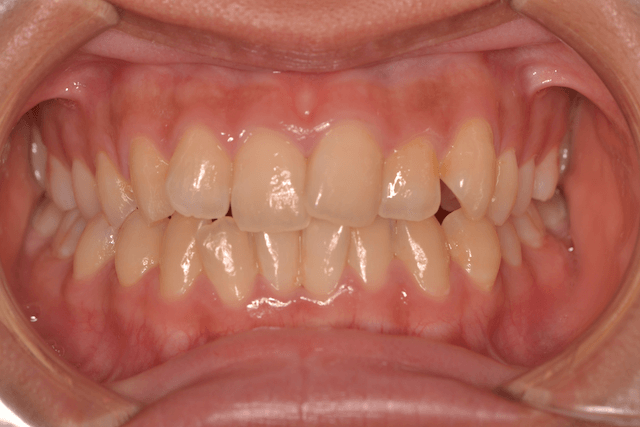

叢生を抜歯とDBSで改善した症例

※DBSとはダイレクトボンディングシステムと呼ばれており、ブラケットにワイヤーを通して歯を動かしていく矯正治療です。

患者情報

17歳女性

主訴

歯並びがガタガタ

行った治療内容

上下顎両側4番抜歯、DBS

治療のリスク

歯肉退縮、歯根吸収

治療期間

動的治療期間3年6か月

※ クリックして拡大することができます。